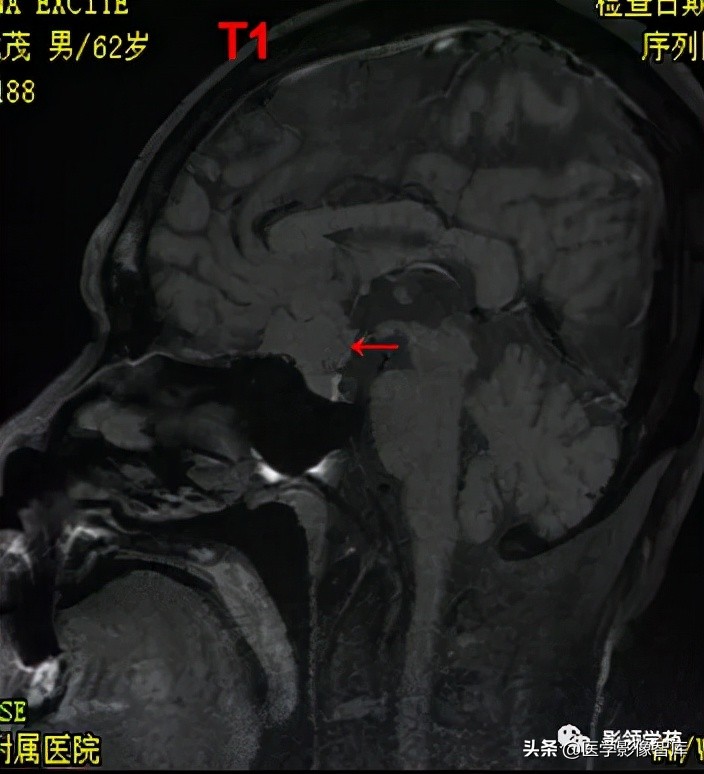

男 62岁,右眼视朦半年

鞍区见一类圆形稍高密度肿块影,密度较均匀,边界较清,位置稍偏右,向上突入鞍上池内,周围骨质未见破坏。

前颅窝底、鞍前区见一肿块影,呈等T1等T2信号,信号均匀,边缘清楚,以宽基底与颅底接触。

病灶呈均匀明显强化(馒头样),见脑膜尾征;肿块后缘部分进入鞍内,挤压垂体前方和视交叉,垂体柄显示不清楚。

右侧大脑前动脉A1段完全被肿瘤包绕;左侧大脑前动脉A1段与肿瘤分界不清,但无明显包绕和推移。双侧海绵窦未见异常征象。